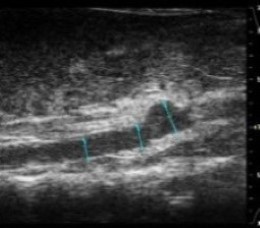

- in vivo VisualSonics Vivo 2100 vascular imaging

Abdominal Echo's performed 24 hours prior to sac using VisualSonics Vivo 2100